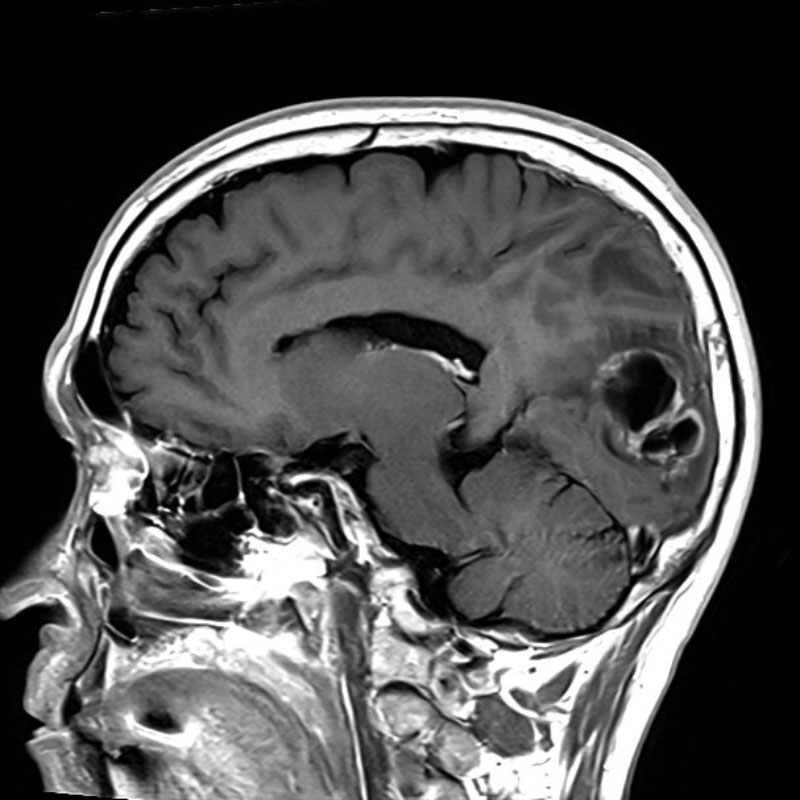

No.’25_26 手術前1

No.’25_26 手術前2